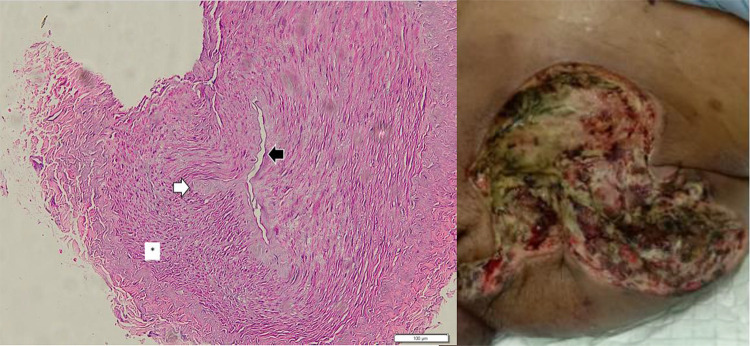

Case: A 65-year-old male with a history of endovascular abdominal aortic aneurysm repair (EVAR) developed left acute limb ischemia (Rutherford category III) and abdominal pain. A CT scan showed significant gas formation around the endograft and complete occlusion of the left distal iliac artery to the femoral arteries. Despite undergoing hip disarticulation and wound care, aortic endograft removal was not possible due to a lack of replacement grafts. Microbiological cultures from arterial pus and urine identified multiple antibiotic-resistant extended-spectrum beta-lactamases (ESBL) producing Escherichia coli. Histopathological analysis of the common femoral artery specimen indicated chronic medium-sized arteritis characterized by endothelial erosion, fibrotic myocytes in the tunica media, and fibrosis of the adventitial layer with inflammatory cell infiltration. The patient succumbed in the ICU 6 days later due to uncontrolled sepsis.

导言:我们介绍了一例晚期内移植物感染病例,感染发展到左侧髂动脉和股动脉,导致左下肢坏疽,患者死亡:一名65岁的男性患者曾接受过血管内腹主动脉瘤修补术(EVAR),后来出现左侧急性肢体缺血(卢瑟福III级)和腹痛。CT 扫描显示内移植物周围有明显气体形成,左侧髂远端动脉至股动脉完全闭塞。尽管进行了髋关节离断术和伤口护理,但由于缺乏替代移植物,主动脉内膜移植物无法移除。从动脉脓液和尿液中进行的微生物培养发现了多种产生耐抗生素广谱β-内酰胺酶(ESBL)的大肠埃希菌。股总动脉标本的组织病理学分析表明,患者患有慢性中型动脉炎,其特征是内皮侵蚀、中膜肌细胞纤维化以及伴有炎性细胞浸润的临近层纤维化。6 天后,患者因败血症无法控制而在重症监护室死亡:讨论:尽管EVAR术后内移植物感染的发生率很低(发病率和死亡率为20%-75%),但其风险很大。感染来源通常是血源性的,源于泌尿道或呼吸道感染,感染延伸至后续动脉的情况非常罕见;感染可能会引起慢性动脉炎症,长期而言可能会导致血栓形成和肢体缺血。本病例强调的是手术后 3 个月出现的低度感染。诊断通常需要通过 CT 血管造影来检测主动脉周围气体或液体。处理高级别感染必须完全切除内移植物,并用抗感染的移植物替代:结论:EVAR术后的内移植物感染虽然罕见,但可能造成严重后果。根据症状和 CT 扫描进行早期诊断。对于高级别感染,移植物内膜移除是金标准疗法,EVAR术后持续随访对预防感染至关重要。